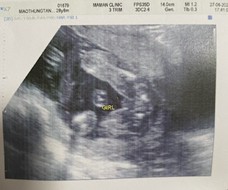

เพศลูก

แบบนี้หมอบอกผู้ชาย แม่ๆคนอื่นๆคิดว่ายังไงค่ะ ผู้ชายชัวร์ๆใช่ไหม อยากได้ผู้ชายมาก

ผู้หญิงจ้า ในใบซาวด์ก็เขียนว่า ว่าFemale คือเพศหญิง

เมื่อวานไปซาวน์แบบนี้เลย เป็นก้อนๆเหมือนไข่หมอบอกผู้ชาย แต่มีความเปลี่ยนไปได้มั้ยที่จะเป็นผู้หญิง จะเชื่อใครดี5555